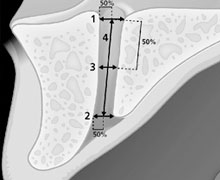

Las dimensiones del CNP, incluyendo la longitud, el ancho a la mitad y el diámetro del foramen incisal y nasal, se midieron en planos sagitales y axiales de CBCT. Además, se realizó una evaluación de los signos de abultamiento, la osteólisis apical del incisivo y su fusión con el CNP.

- Figura 1: Vista esquemática de las diferentes medidas realizadas en los planos sagitales de las imágenes CBCT (nº 1 a nº 4).